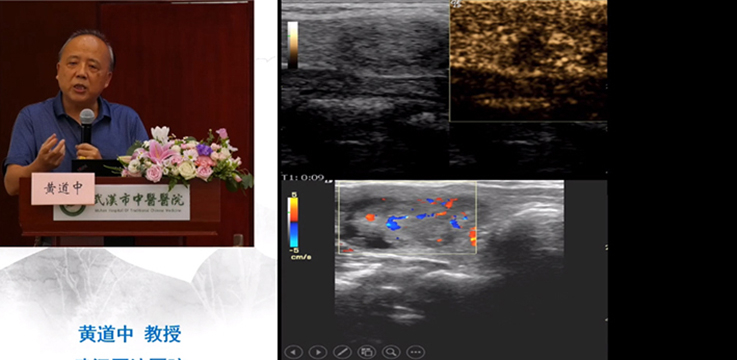

會上黃道中教授、楊順實教授、余曉梅教授、曾書娥教授、彭國平教授、閔潔醫(yī)師作了主旨演講,分享了他們的經(jīng)驗,并同各位學(xué)員進行了案例討論。